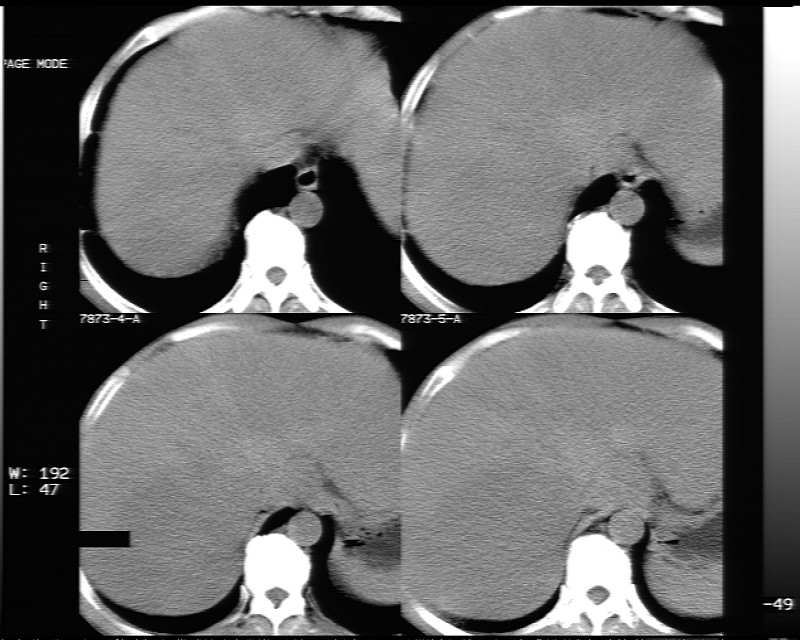

平扫示:

局灶性脂肪肝

不均匀性脂肪肝

非均质性脂肪肝。

支持脂肪肝【无占位性,高低密度区同期强化,平扫与强化的密度成比例】